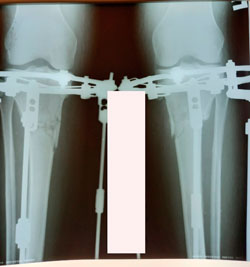

Исходник - 47 лет.

Дата операции - 11.11.2020

image-10-11-20-02-28-5.gif

image-10-11-20-02-28-2.gif

image-10-11-20-02-28-1.gif